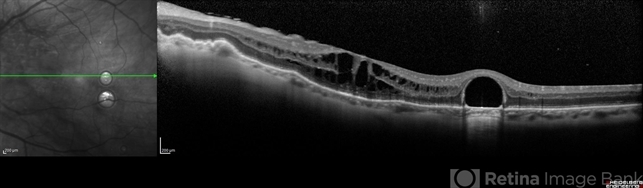

- macular edema, post-vitrectomy, retained perfluorocarbon

- Optical coherence tomography system

- SD-OCT and HRA from a 42-year-old patient after silicon oil removal. The image shows macular edema and retained perfluorcarbon.